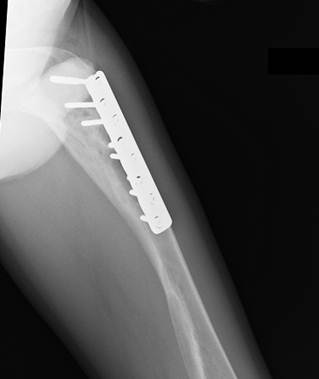

Сросшийся

перелом бедра у мальчика 13 лет с несовершенным остеогенезом, остеосинтез простой пластиной со множеством

винтов. Видна типичная деформация

бедренной кости по типу «галифе», следы

неоднократных переломов в прошлом.

Применение операции Богданова в

возрасте 5- 6 лет позволило бы избежать этих негативных явлений и предотвратить

переломы.